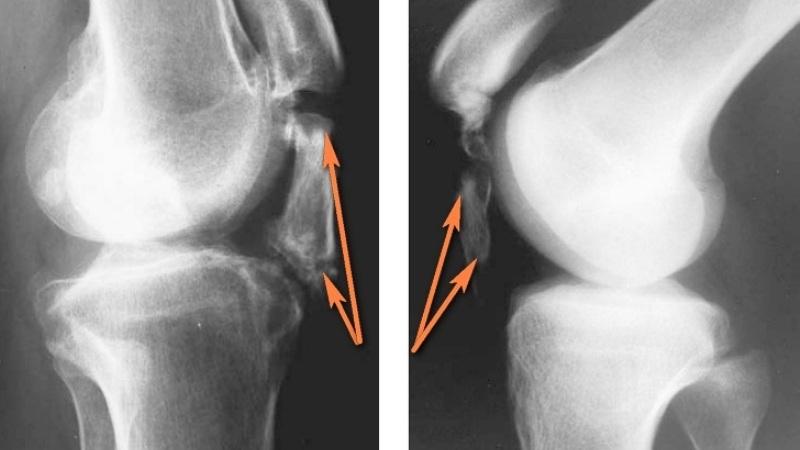

Для успешного восстановления после операции необходимо сделать рентгеновский снимок поврежденной области. При соблюдении всех рекомендаций по лечению, пациенты смогут вернуться к своему обычному образу жизни.

После того как острые симптомы утихнут, проводится полное обследование с использованием компьютерной томографии и магнитно-резонансной томографии.